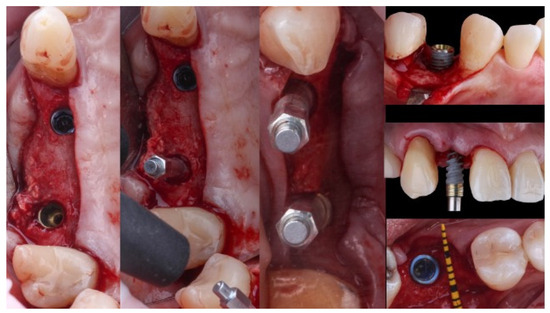

2. Materials and Methods

2.3. Surgical Protocol